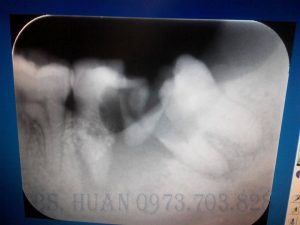

Ca này chỉ đơn thuần là răng 8 nghiêng gần, tuy nhiên cần loại bỏ sớm để tránh gây hỏng răng 7.

Ca này cũng là răng 8 nghiêng gần, nhưng không xử lý sớm dẫn tới việc hư tổn răng 7 và phải nhổ cả 2